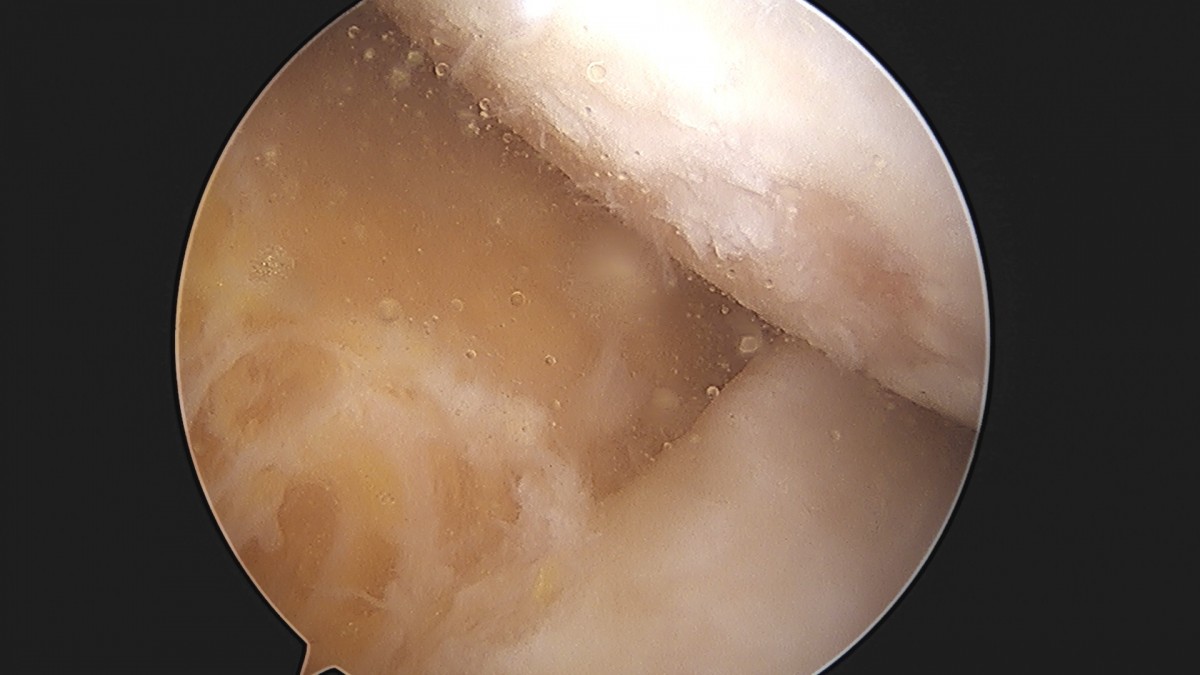

이재상원장님 무릎 반월상 연골판 절제술 김민O 환자

작성자 최고관리자 댓글 0건 조회 365회 작성일 25-09-16 16:10